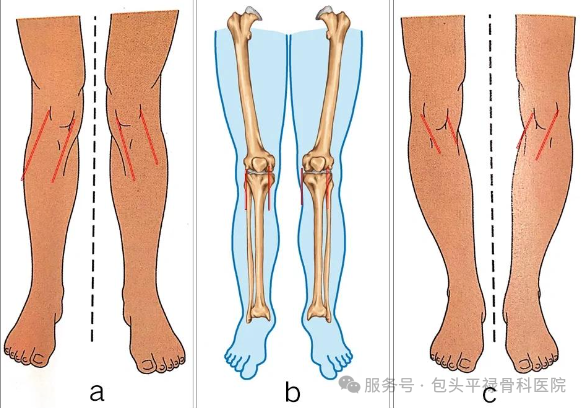

膝关节畸形不严重

内翻(O型腿)≤15度、外翻(X型腿)或屈曲畸形≤10度,且可被动矫正。